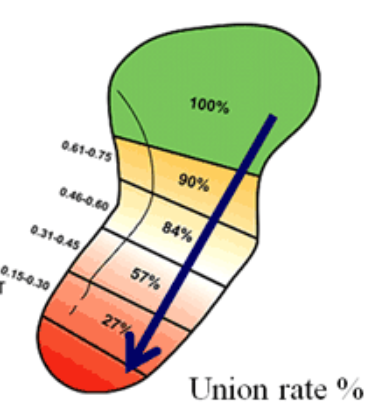

- 주상골 골절은 골절의 위치에 따라 대략적으로 근위부, 요부(허리, 중간), 원위부 골절로 나누며, 그 치료 방법과 예후가 달라지게됩니다.

- 근위부(손목에 가까운 부분) : 20~25%, 혈류가 끝까지 잘 가지 않을 수 있어 예후가 좋지 않습니다.

- 요부(주상골 중간) : 60%, 2달정도 CAST

- 원위부(손목에서 먼 부분) : 10~20%, 혈류가 가까워서 예후가 좋습니다.

- 합병증으로서 가장 많은 것은 골절의 불유합으로 근위부 골절시 많이 일어납니다. 후에 10년-15년이 지나면 외상성 관절염이 발생할 수도 있습니다. 부정유합이나 손목관절 불안정성이 나타날 수 있습니다.